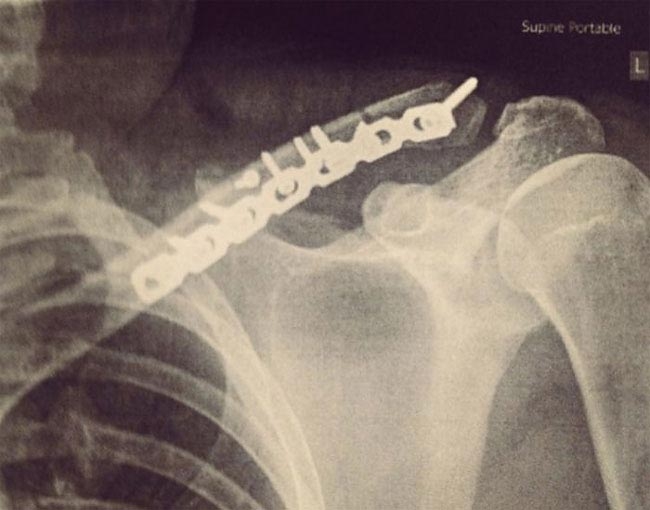

"Через 3 дня я был выписан из больницы со шрамом и рентгеновскими снимками, один из которых выглядел вот так. Металлическая пластина скрепляла мою ключицу в течение всего следующего года, пока окончательно не срослась. Несмотря на это у меня всего один раз был разговор со службой безопасности аэропорта — отличная работа, Берлин"